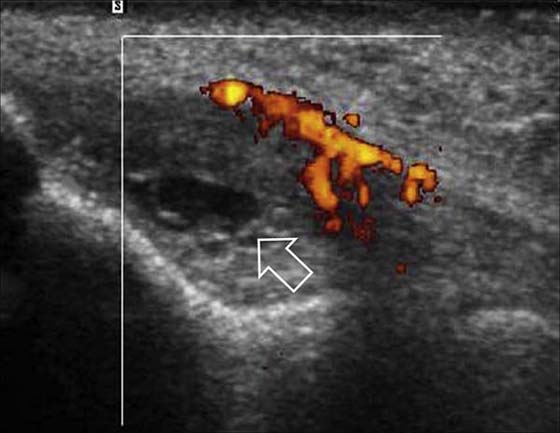

Lateral epicondylitis, or “tennis elbow,” is a chronic tendinopathy of the common extensor origin and is a frequent cause of lateral elbow pain. On MRI, abnormal high signal is seen at the common extensor origin on fluid-sensitive sequences, sometimes with associated partial tears, which are fluid-bright.29 In more severe cases, associated subtendinous bone marrow edema may be present at the lateral epicondyle, but this is not required for radiologic diagnosis. US is a valuable modality for examining the lateral epicondyle.30,31 Sonographic features include common extensor origin thickening, heterogeneous echogenicity, calcific deposits, partial tears, and hypervascularity on Doppler imaging (Fig. 14-12). US may also be used to guide steroid or anesthetic injections and tendon fenestration.32 Medial epicondylitis has similar MRI and US findings at the common flexor origin. Both of these entities may be associated with injury to the adjacent medial and lateral stabilizing structures.33 Evaluation of the other tendons, including the biceps, triceps, and brachialis, is optimized with MRI. US is also useful for directed examination of tendon pathology at the elbow.

images

Figure 14-12 Lateral epicondylitis or common extensor tendinosis with partial tear. Ultrasound image demonstrates thickening of the common extensor origin consistent with tendinosis/epicondylitis with an associated hypoechoic (black) defect within the extensor tendon origin consistent with an interstitial partial tear (arrow). Power Doppler imaging demonstrates hypervascularity (orange areas), often seen with lateral epicondylitis/common extensor tendinosis.